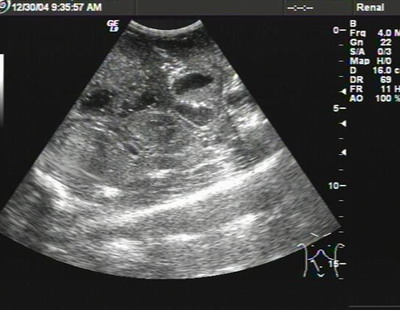

B超:小肠普遍均匀性增厚(0.6cm),

肠间隙少量积液

--低蛋白所致肠壁水肿?

B超影象